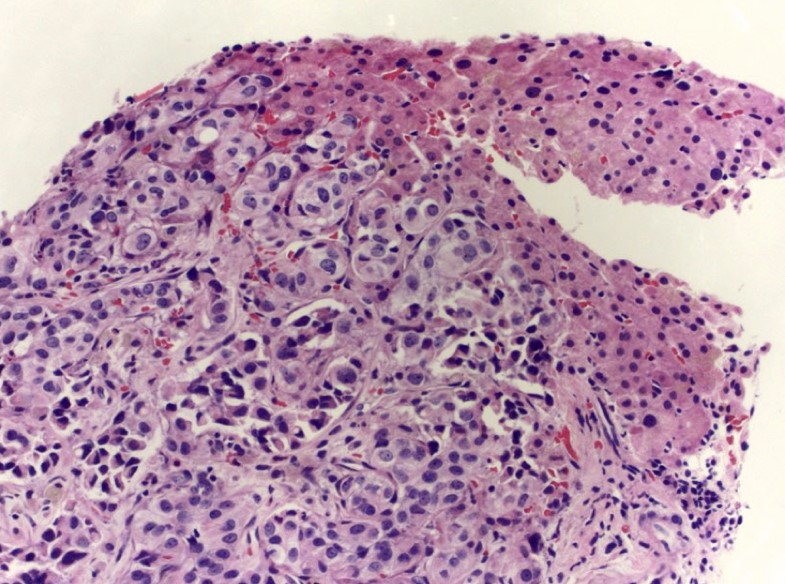

Microscopic (histologic) images

Contributed by Emily S. Reisenbichler, M.D., Andrey Bychkov, M.D., Ph.D., Maria Tretiakova, M.D., Ph.D. and Debra Zynger, M.D.

Positive staining - tumors

- Breast cancer, invasive (72 - 94%) (Mod Pathol 2010;23:654, Am J Clin Pathol 2012;138:57), well differentiated > poorly differentiated; more sensitive than GCDFP-15 and mammoglobin in staining of metastatic breast carcinoma (Ann Diagn Pathol 2015;19:6)

- Primary and metastatic urothelial carcinoma (67 - 93%) (Am J Surg Pathol 2007;31:673, Am J Surg Pathol 2013;37:1876)